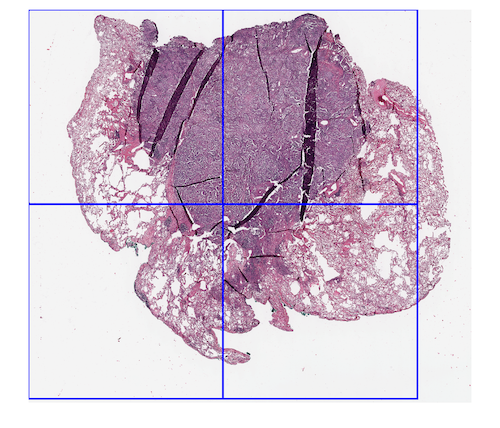

To evaluate the generalization and the practical performance, we also selected five WSIs from the NIH dataset222https://gdc.cancer.gov. We selected WSIs from three different organs (kidney,lung and colon). Figure 3 shows two sample WSIs alongside the boundary boxes of our classifier.

Classifiers, which are trained on small datasets predominantly fail to generalize on new classification categories. In our experiments, we selected five new WSIs with a noticeable amount of folded tissue from the NIH dataset to evaluate the ability of deep features and SVM to generalize to unseen cases. We applied our method in different window sizes with no overlap. All patches will be resized to before feeding to the network. Figure 3 shows sample WSIs from NIH database with different window sizes. Blue boxes are representative of the presence of folded tissue while a yellow box represents normal tissue. The overall accuracy in generalization test set with pixel size dropped to . A possible explanation for this result may be the lack of adequate fold pattern samples in the training set. Besides the difference in an organ type, scanner brand should also be considered. However, as we trained and tested the classifiers for patch-wise tissue detection, one has to bear in mind that the detection of one tissue fold is sufficient to flag a scan for visual inspection.

It can be seen in Figure 3(b) that there is a folded patch which has not been detected. There might be some justifications for this false negative -yellow window in Figure 3 (b)-. The first one is that our training dataset enclosed the entire folded tissue within each patch (i.e., no folded tissue was split between two patches). In this false negative example, however, the patch does not contain all of the folded tissue, and parts of the folded tissue are contained within the neighbouring patches. The same error has occurred in Figure 3(c). The second justification is that the training patch sizes were about 5000 by 5000 pixels, while the experiment window size was 1500 by 1500, therefore training with bigger size patches (patch in lower magnification) might have been the reason for false negatives.